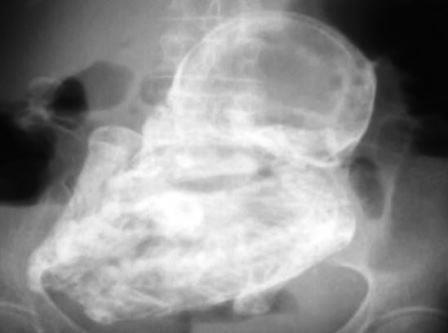

| Hình ảnh "bào thai đá" trong bụng bà cụ 76 tuổi. |

Trưa 24-3, bác sĩ Lê Quang Vinh, PGĐ - Bệnh viện Đa khoa khu vực Cam Ranh cho biết, vừa đưa cụ bà 76 tuổi, được chẩn đoán có thai chết lưu trong ổ bụng “thai đá” ra Bệnh viện Đa khoa tỉnh Khánh Hòa để chụp MRI, nhằm xác định khối thai có ảnh hưởng gì đến các bộ phận cơ thể xung quanh, qua đó có hướng giải quyết phù hợp và tốt nhất cho sức khỏe của cụ bà. Tuy nhiên, kết quả phải đợi đến chiều tối nay, hoặc sáng mai (25-3) sẽ có kết quả cụ thể.

Trước đó, lãnh đạo Bệnh viện Đa khoa thành phố Cam Ranh (tỉnh Khánh Hòa) cho biết, bệnh viện đã phát hiện cụ bà 76 tuổi (trú tại phường Cam Lộc, TP Cam Ranh) mang trong bụng một bào thai đã chết lưu từ rất lâu. Cũng theo vị bác sĩ này, đây là trường hợp hiếm gặp, rất hy hữu trong y khoa của thế giới.

Theo thông tin ban đầu, khi đi khám, cụ bà nói rằng, gần đây bà cảm thấy đau vùng thắt lưng nên mới đến Bệnh viện Đa khoa Cam Ranh để khám bệnh. Kết quả chụp phim X-quang cho thấy, có hình hài bào thai nằm trong ổ bụng của bà. Các bác sĩ dự đoán, bào thai này rất có thể đã hình thành cách đây gần 30 năm trước.